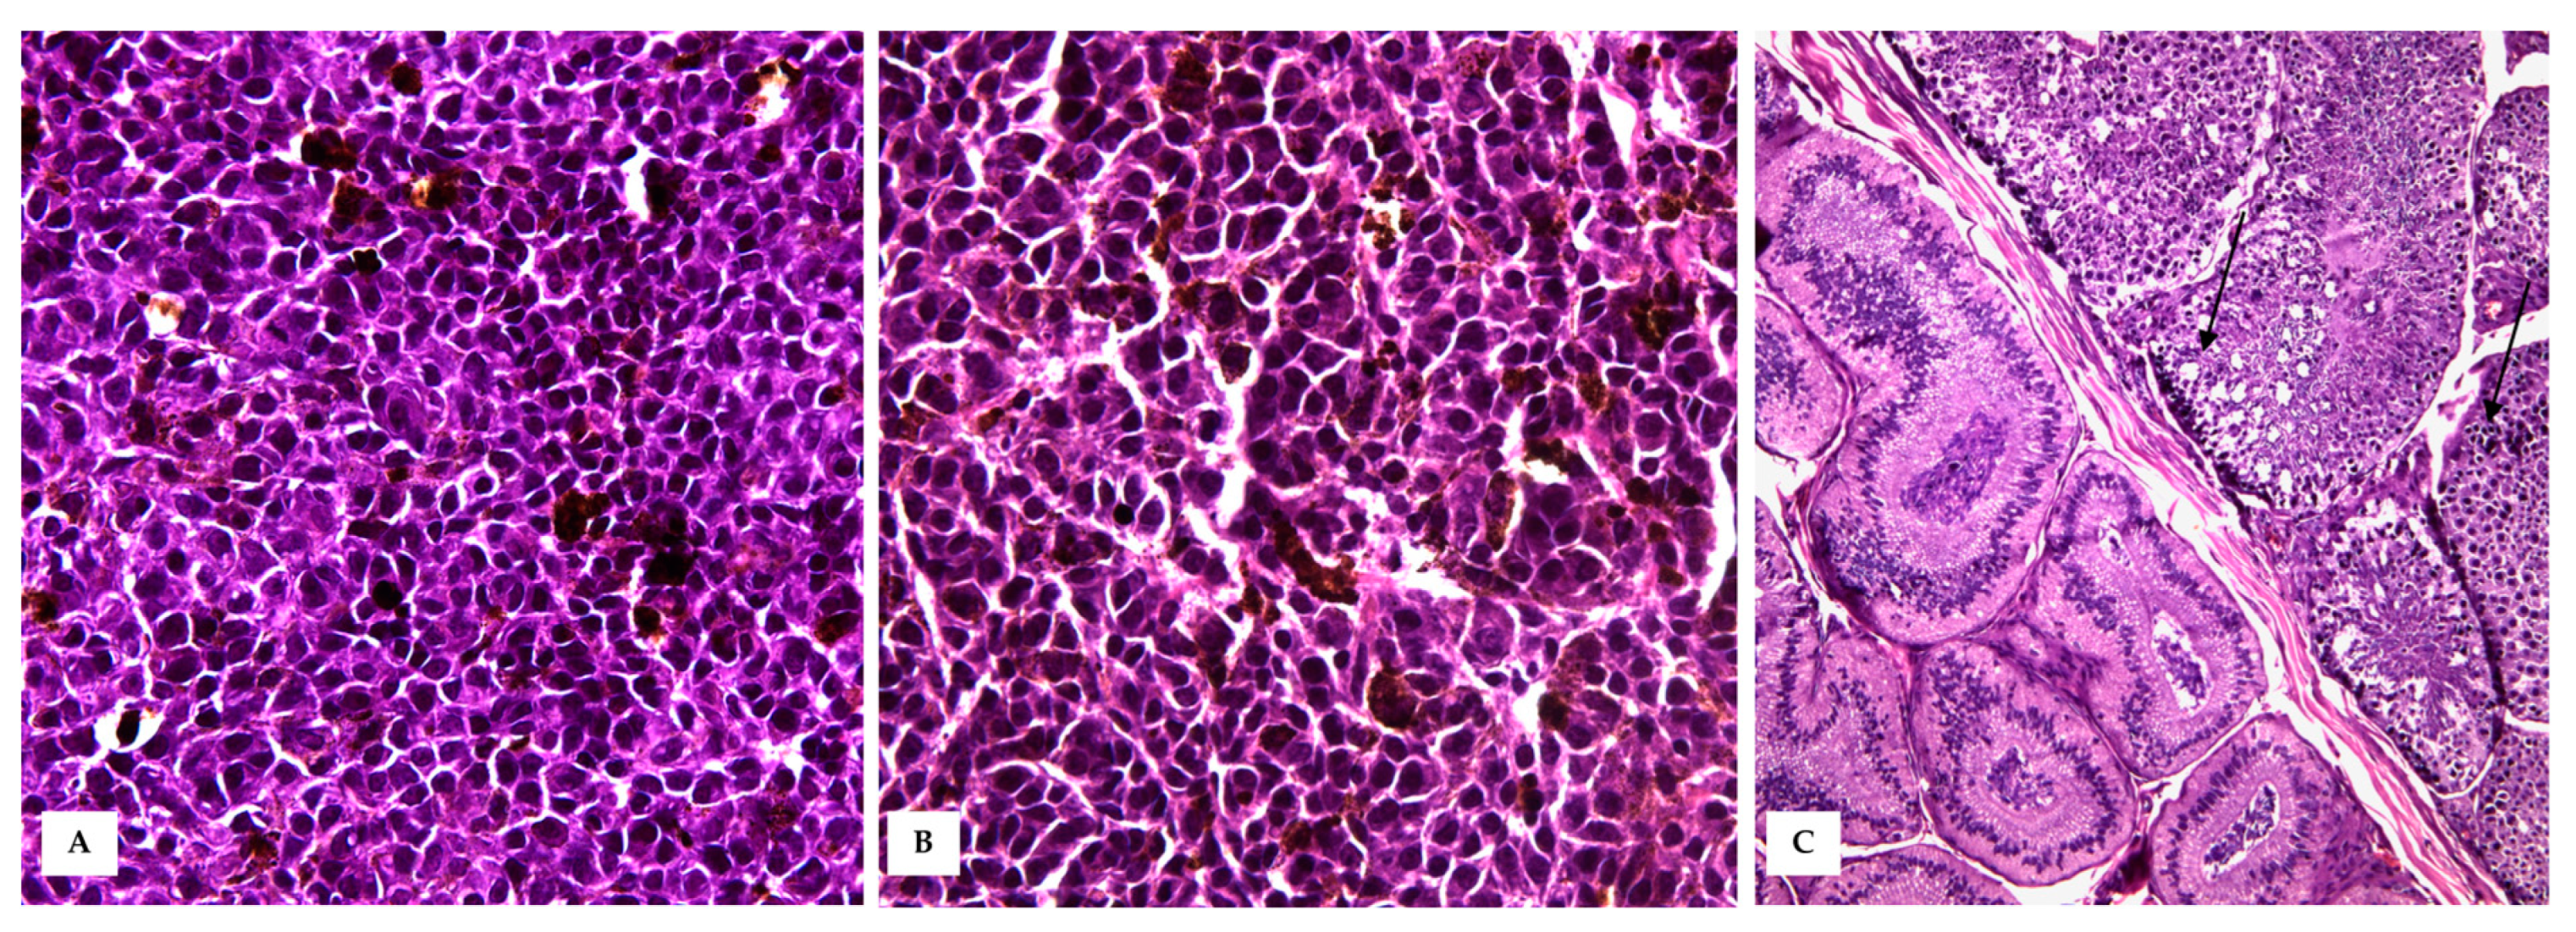

The testis was delimited by a thin tunica albuginea, and the testicular parenchyma was largely obscured in its morphology by densely packed neoplastic cells. Occasionally, markedly expanded seminiferous tubules, lined with a thin basement membrane and filled with polygonal neoplastic cells mixed with scattered degenerated spermatogenic cells were observed (Figure 5).

Figure 5. Testicular metastasis. (A,B) Densely packed polygonal- to spindle-shaped neoplastic melanocytes arranged in sheets, obscuring testicular morphology (HE, 40×). (C) Occasionally, markedly expanded seminiferous tubules (black arrows) were observed, lined with a thin basement membrane and filled with polygonal neoplastic cells and degenerated spermatogenic cells (HE, 20×).